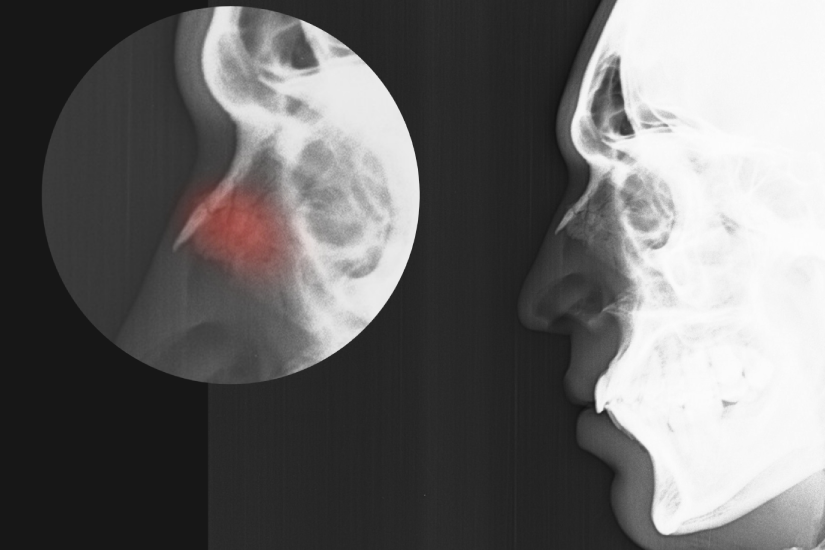

Diagnosticul unei fracturi de piramidă nazală este stabilit de medicul specialist ORL în urma unei evaluări care combină examinarea fizică cu investigațiile imagistice.

Identificarea corectă a tipului de fractură permite alegerea celei mai bune metode de tratament, fie că este vorba despre monitorizare sau intervenție chirurgicală.

Diagnosticul se stabilește prin:

- Examen clinic detaliat pentru evaluarea aspectului exterior și palparea zonelor sensibile.

- Examinarea internă a cavității nazale pentru verificarea septului.

- Radiografia de piramidă nazală, pentru confirmarea liniilor de fractură osoasă.

- Tomografia computerizată (CT), pentru vizualizarea detaliată a traumatismelor complexe.

Hematomul septal: o urgență medicală

Hematomul septal reprezintă o acumulare de sânge între cartilaj și mucoasă, fiind o urgență care necesită drenaj imediat.

Dacă nu este tratat în câteva ore, sângele comprimă vasele care hrănesc cartilajul, ducând la necroză și prăbușirea suportului nazal.

- Hematomul are aspect de umflătură roșiatică în interiorul nasului, care blochează complet aerul.

- Există riscul apariției așa-numitului „nas în șa", prin pierderea suportului cartilaginos.

- Dacă intervine infecția, se instalează pericolul de perforație septală sau abces.